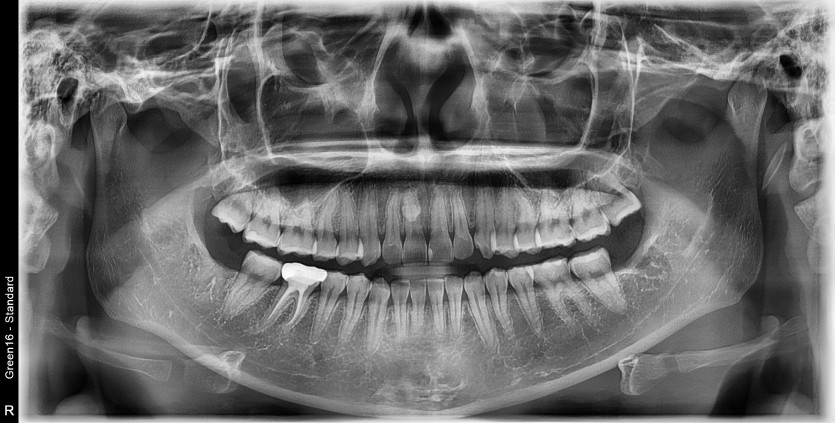

#38,48 사랑니 발치

구강 외과 전문의가 당일 발치했습니다.